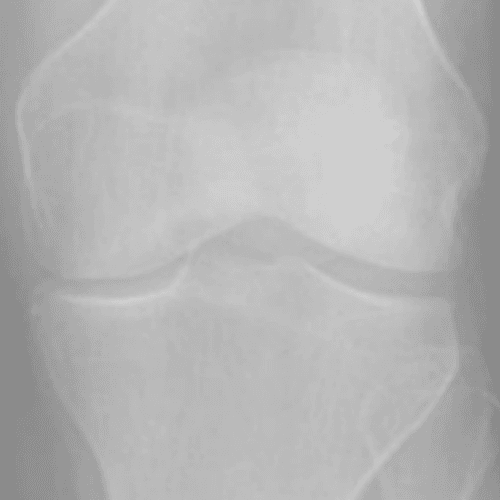

Kellgren and lawrence (KL) Grading System

통증이 발생한 무릎을 x-ray로 촬용한 관절염 결과를 총 4단계로 구분한 것을 KL Grading System 이라고 부르며

2~3단계의 환자들에게 무릎 연골 줄기세포 시술을 진행합니다.

Grade 1

연골이 손상되기 시작하여 미약한 골극이 보임

Grade 2

연골 손상이 진행되어 골극이 두드러지기 시작함